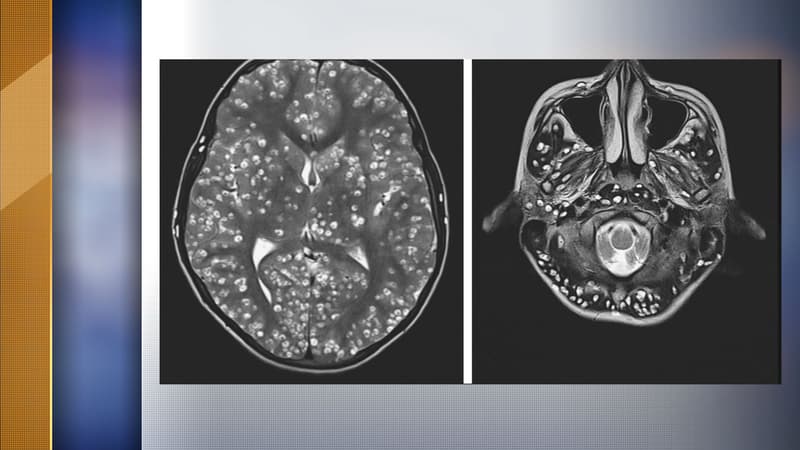

Un jeune Indien meurt des suites d'une infestation de larves dans son système nerveux

Des images de l'infestation - NEJM / Twitter

Selon le Midi Libre, qui relaie également l'affaire, le jeune homme aurait été pris de vertiges en plus d'être victime d'un gonflement des yeux et d'une douleur à l'aine. Et c'est lors d'examens poussés que le corps médical a découvert l'affreuse réalité, l'infection s'était propagée, comme on peut le constater sur les photos ci-dessous, à l'ensemble du système nerveux, mais également dans un œil et un testicule.